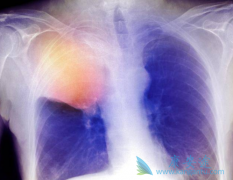

肺癌是现在比较常见的癌症之一。肺癌是由很多的因素引起的,但是不管是什么原因,肺癌对于人体来说伤害都是巨大的。治疗肺癌的药物非常多,易瑞沙(吉非替尼)就是其中的一种,不过服用吉非替尼会出现一些不良反应,临床上,患者服用易瑞沙后常见的不良 ...

肺癌患者出现脑转移是一个严重且难于治疗的棘手问题。因为脑转移不同于骨转移,骨转移充其量是疼痛〔也有个别人没有痛感〕、病理性骨折及最严重的下身或全身瘫痪,但还不致于要病人的命;而脑转移就不同了,如果没有及时处理,用药不对症或者方法使用不 ...